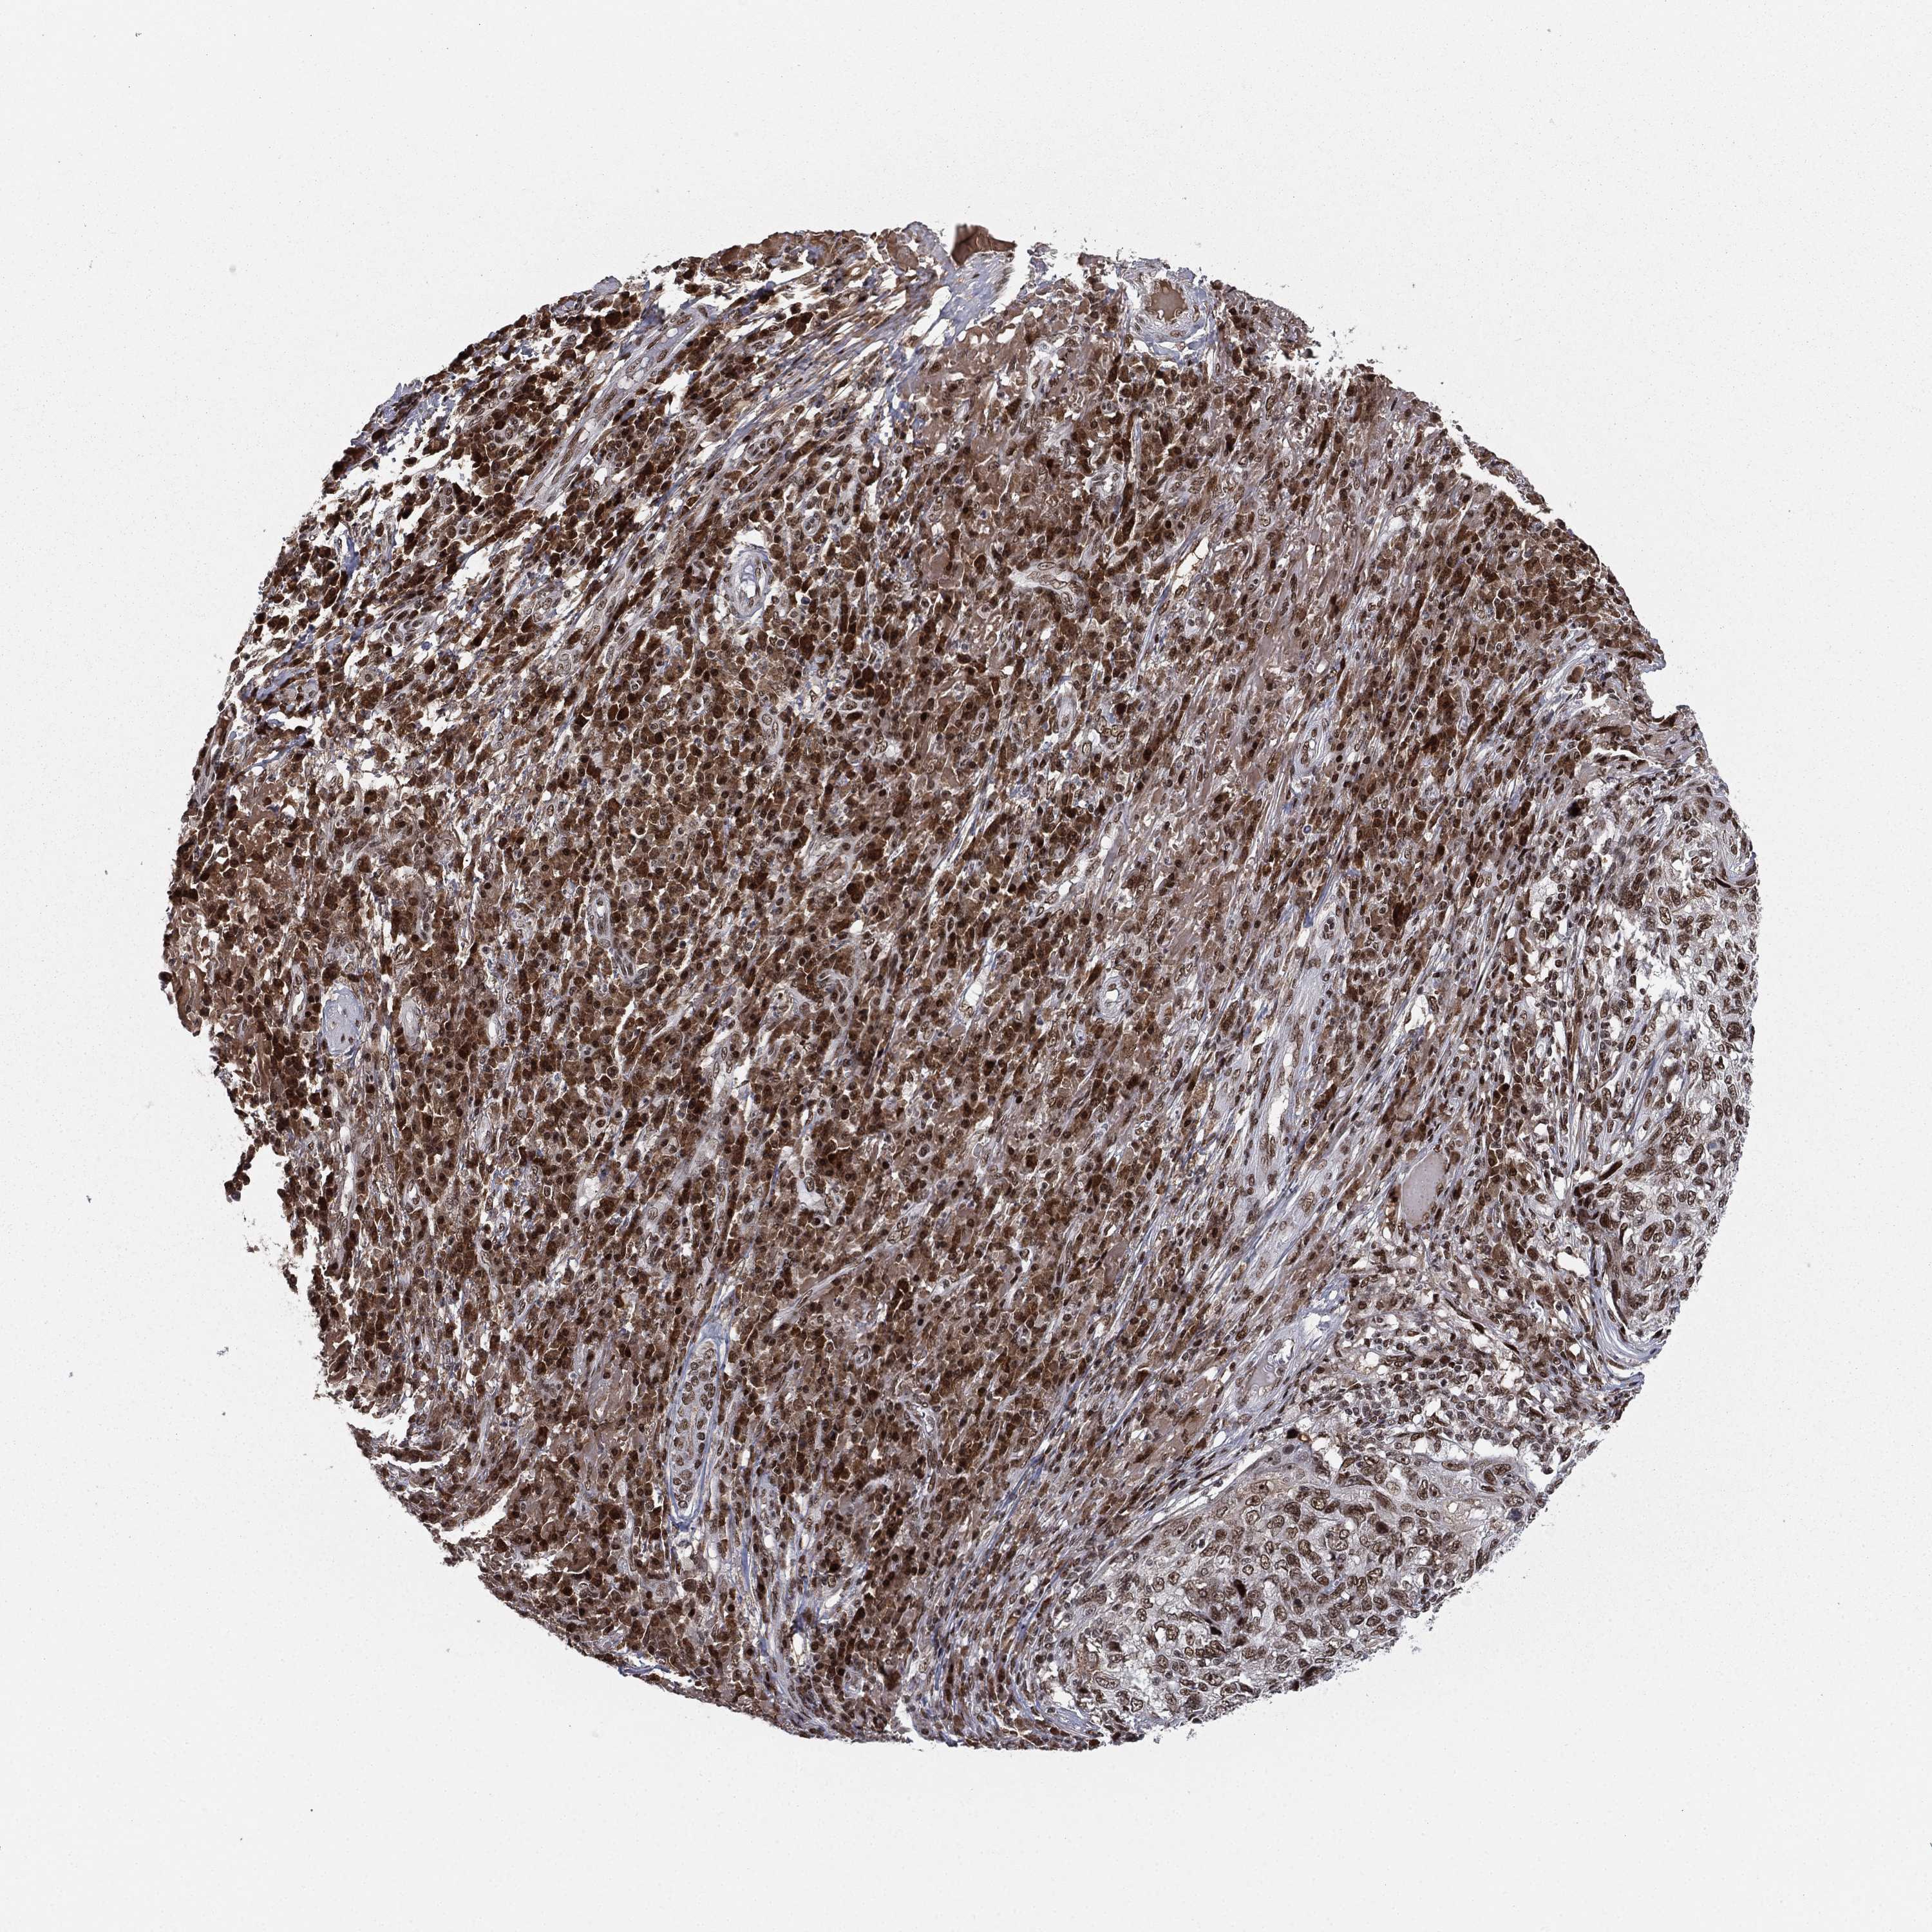

SKIN CANCER - Protein expressioni

A mouse-over function shows sample information and annotation data. Click on an image to view it in a full screen mode. Samples can be filtered based on level of antibody staining by selecting one or several of the following categories: high, medium, low and not detected. The assay and annotation is described here.

Antibody stainingi

Antibody staining in the annotated cell types in the current human tissue is reported as not detected, low, medium, or high, based on conventional immunohistochemistry profiling in selected tissues. This score is based on the combination of the staining intensity and fraction of stained cells.

Each image is clickable and will lead to virtual microscopy that enables deeper exploration of all samples and also displays staining intensity scores, fraction scores and subcellular localization as well as patient and tissue information for each sample.

Antibody CAB079946

Squamous cell carcinoma, NOS